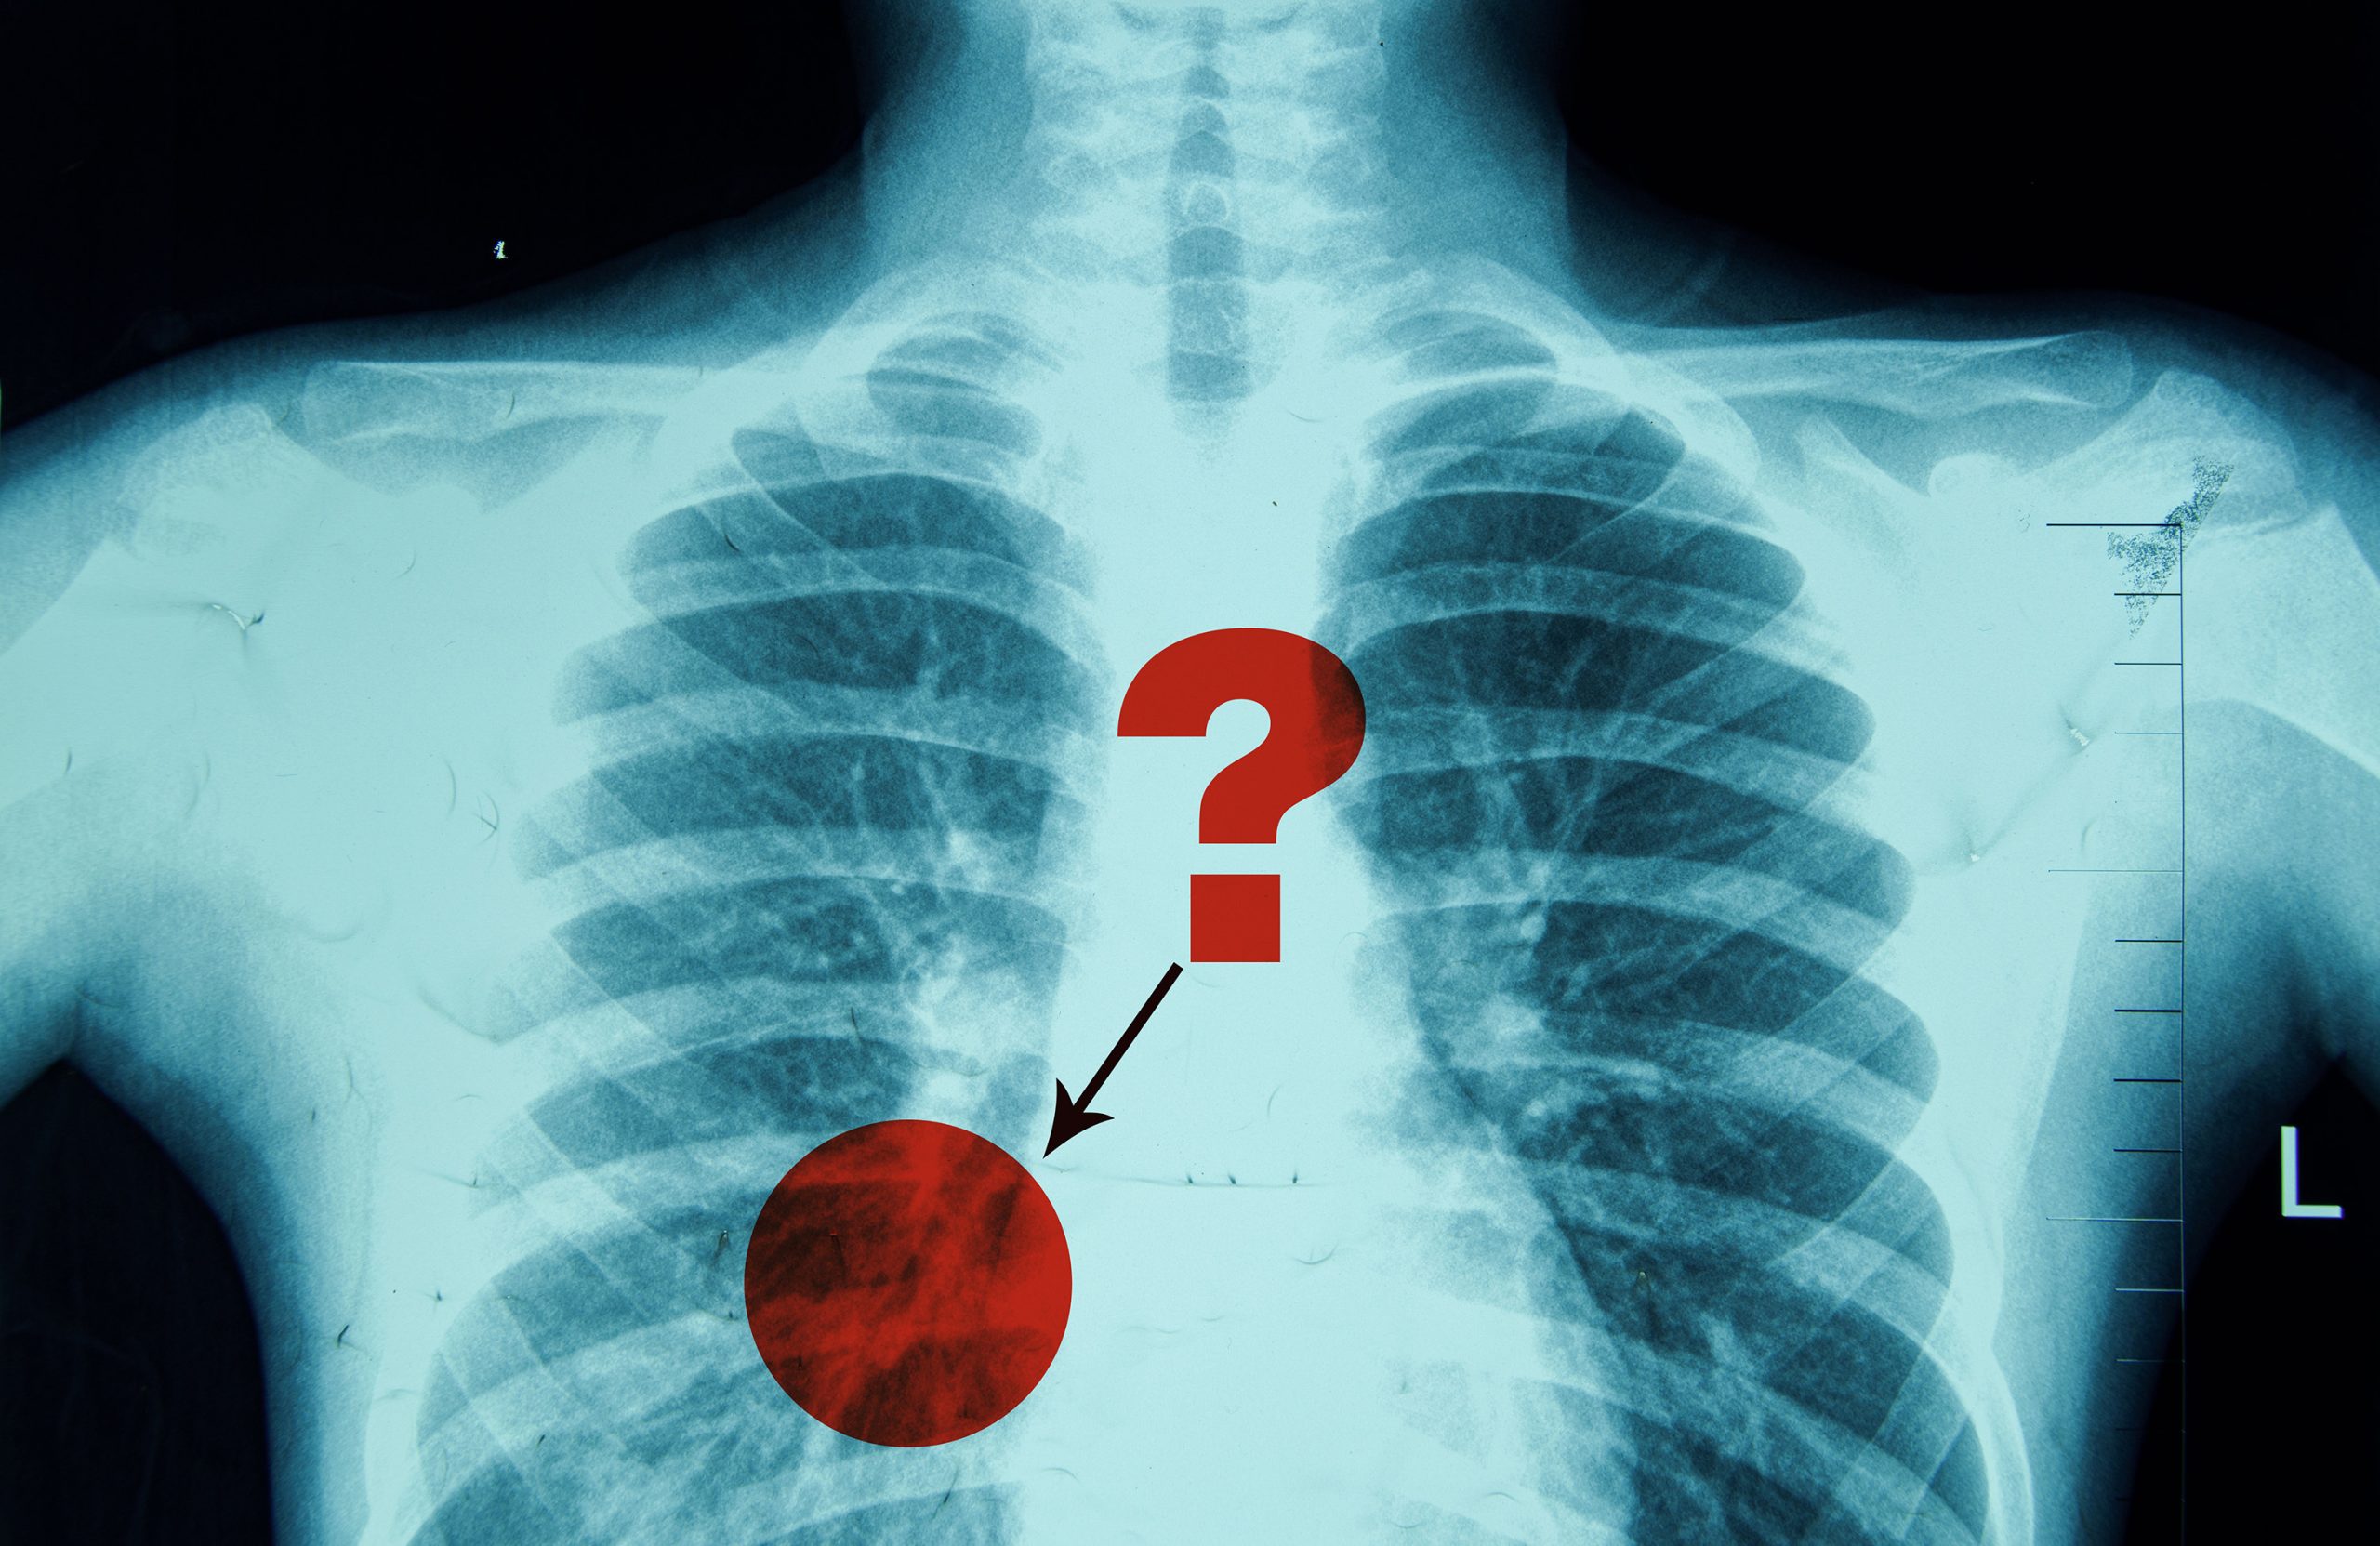

Due to the inherent ambiguity in medical images like X-rays, radiologists often use words like “may” or “likely” when describing the presence of a certain pathology, such as pneumonia.

A radiologist writing a report about a chest X-ray might say the image shows a “possible” pneumonia, which is an infection that inflames the air sacs in the lungs. In that case, a doctor could order a follow-up CT scan to confirm the diagnosis.